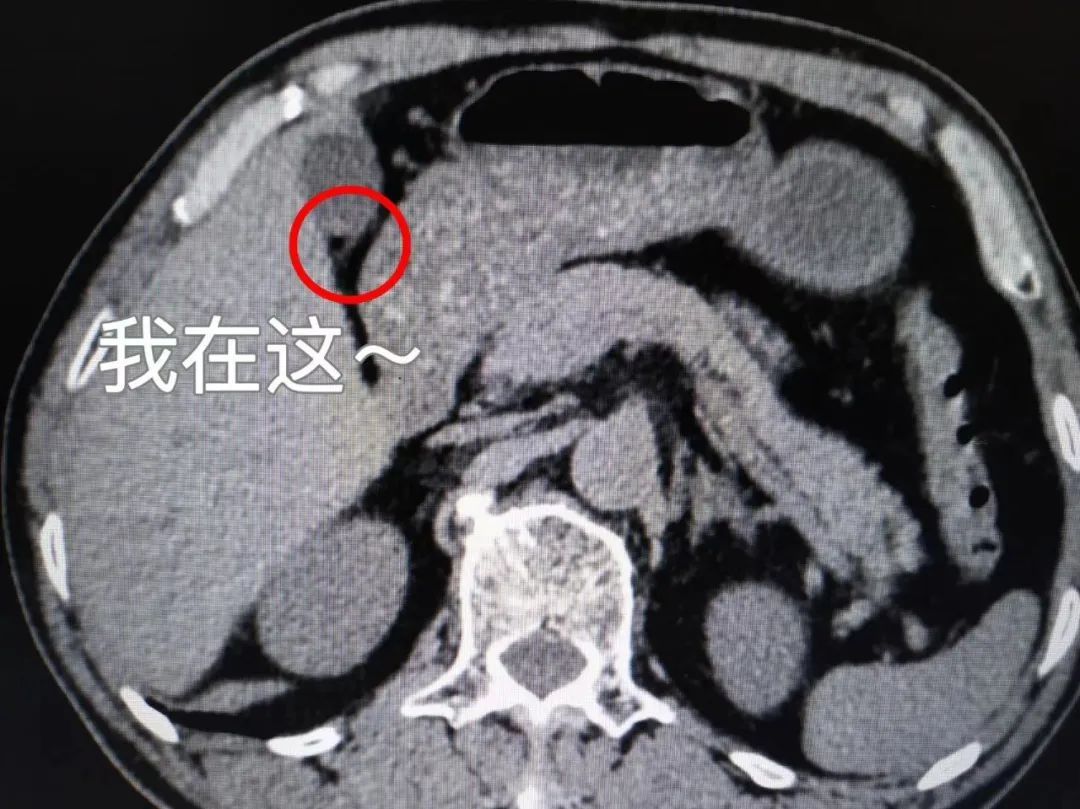

胆囊阴性结石

就是等密度胆固醇结石(CT上表现与胆汁密度一致)或低密度胆固醇结石(CT上表现为低密度):CT表现为低密度、等密度充盈缺损,单发或多发,类圆形或多角形;CT值在40Hu以下,变换体位结石位置有变动,少数与胆囊壁粘连者不能移动。